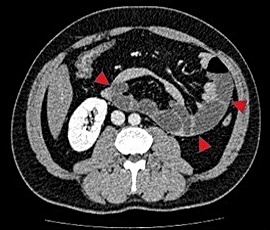

[内ヘルニア(傍十二指腸ヘルニア)] 手術:腹腔鏡下ヘルニア手術

CT画像